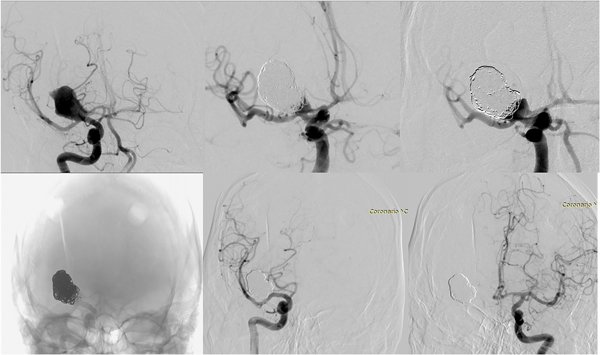

Caso clínico: Paciente sexo masculino de 44 años, consulta por debilidad en hemicuerpo izquierdo acompañada de cefalea. Examen físico: hemiparesia braquiocrural izquierda 4/5. TC DE CEREBRO: imagen espontáneamente hiperdensa en territorio de ACI con edema perilesional, desplazamiento de línea media e hidrocefalia. ANGIOGRAFÍA CEREBRAL: aneurisma sacular disecante gigante parcialmente trombosado dirigido hacia arriba de 27 x 20 mm con cuello ancho de 8 mm que involucra tip carotídeo derecho. Se procede con clipado microquirúrgico, no obstante durante la cirugía se observa origen de arteria cerebral media involucrado en parte del saco. Posteriormente paciente presenta ruptura aneurismática, se planifica tratamiento endovascular: embolización con coils en agudo y dispositivo diversor de flujo en diferido.

Discusión: Las opciones terapéuticas son: clipado microquirúrgico, complejo debido a la presencia de múltiples arterias perforantes en relación al saco aneurismático; tratamiento con coils como única técnica, muestra altas tasas de recanalización y retratamiento; embolización con coils asistida por stent no diversor de flujo y el uso del dispositivo WEB con tasas de oclusión del 61% y 76% respectivamente. El uso de dispositivos diversores de flujo presenta mejores tasas de oclusión y bajas tasas de retratamiento. Su uso en etapa aguda es limitado por el riesgo de resangrado (4%). Un paradigma de tratamiento para aneurismas accidentados, es la embolización con coils en la etapa aguda para prevenir el resangrado temprano, seguida de la colocación planificada de un dispositivo diversor de flujo.

Conclusión: La introducción de dispositivos diversores de flujo ha revolucionado el manejo neurointervencionista de aneurismas gigantes, complejos, con relación cuello-domo desfavorable.